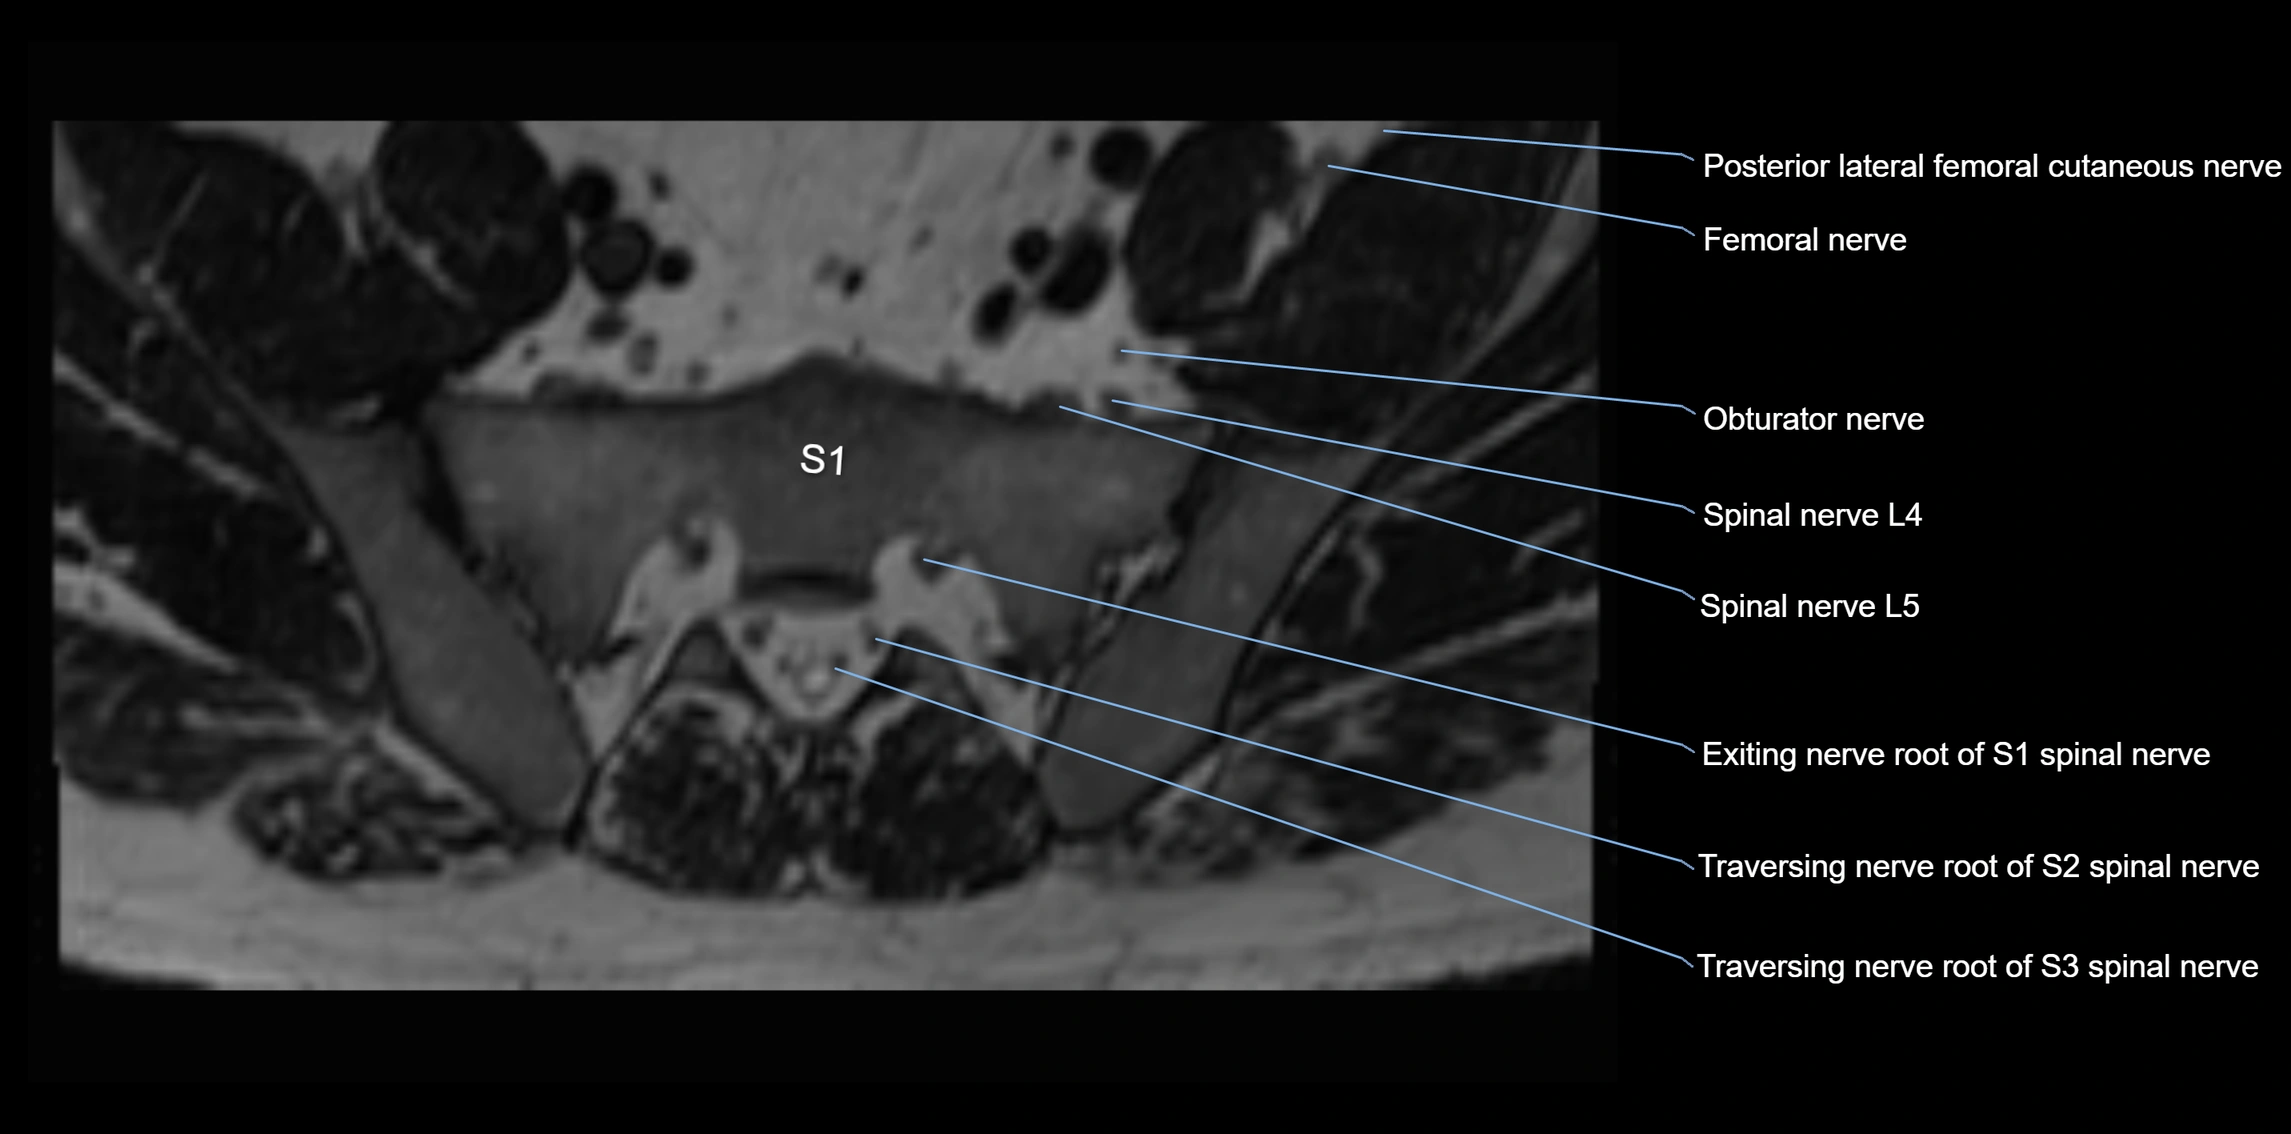

MRI image

image